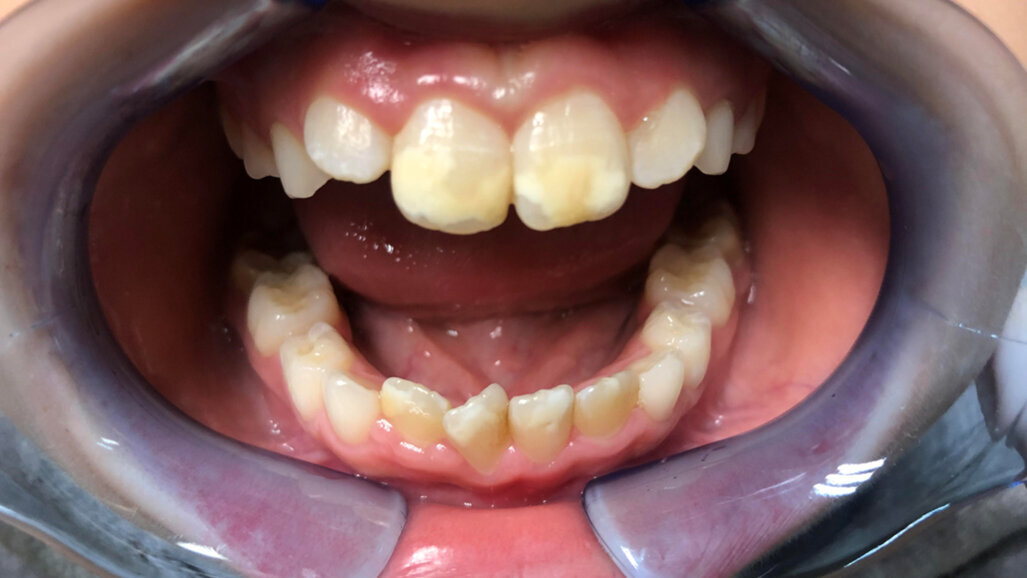

Hipomineralizarea molarilor-incisivilor – sindromul de hipomineralizare molar-incisiv (MIH) – este recunoscută tot mai frecvent ca o provocare semnificativă în stomatologia pediatrică. Afectând copiii la nivel global, MIH se manifestă prin defecte ale smalțului la primii molari permanenți și la incisivi, cu o prevalență globală estimată între 10% și 20%.

Din punct de vedere clinic, MIH reprezintă o problemă complexă. Copiii afectați pot prezenta opacități ale smalțului, distrugerea smalțului post-erupție, hipersensibilitate dentinară și un risc crescut de carii dentare. Aceste simptome pot afecta funcționalitatea orală și calitatea vieții. În ortodonție, MIH complică tratamentul: smalțul fragil crește riscul de dezlipire a bracketurilor, iar molarii sever compromiși pot necesita extracții, ceea ce poate întârzia sau modifica planurile de tratament ortodontic. Având în vedere faptul că evaluările ortodontice precoce coincid adesea cu erupția primilor molari permanenți, ortodonții sunt frecvent primii care identifică MIH, fiind astfel în prima linie a gestionării acestei afecțiuni.